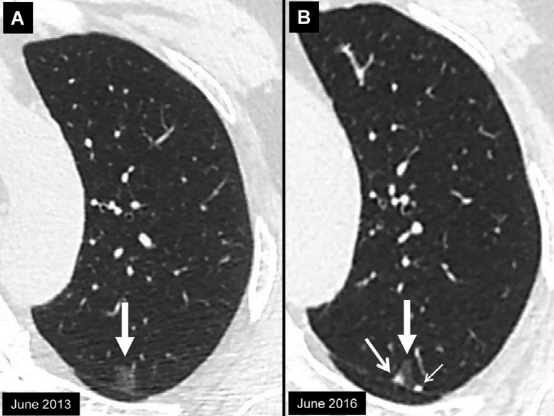

右肺上叶亚实性结节。结节的实性成分定义不清,导致由两位放射科医生进行的测量不一致。实性成分的两个长轴直径分别为图B、28 mm和图C、14 mm。根据临床意义,我们推荐使用较大的长轴直径。在此图中只显示了实性成分的测量,但在临床实践中,必须对总体结节和实性成分进行测量。